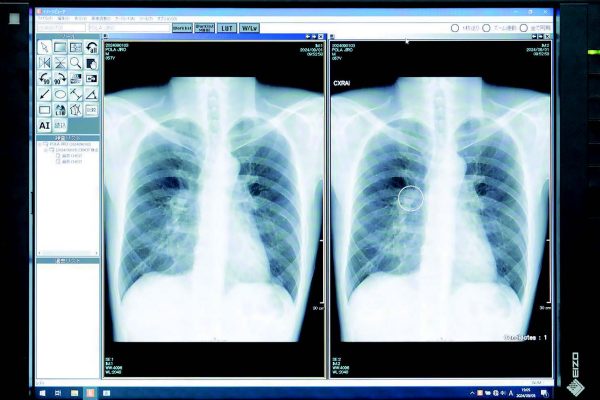

A3.専門医の読影スキルを学習したAIが病変の見落とし防止を支援します。たとえば肺がんが疑われる所見である結節影や、肺炎や結核など感染症の所見である浸潤影、これらの見落とし防止をお手伝いします。忙しい日常診療のなか、読影にかける時間を短縮させ、専門外診断の不安や一人で読影を行う心理的負担を軽減させるなど、開業医を強力にサポートします。

図1 左はAI解析前画像 右は解析後画像 解析後画像は指摘箇所を○で表示、指摘数が右下に表示される